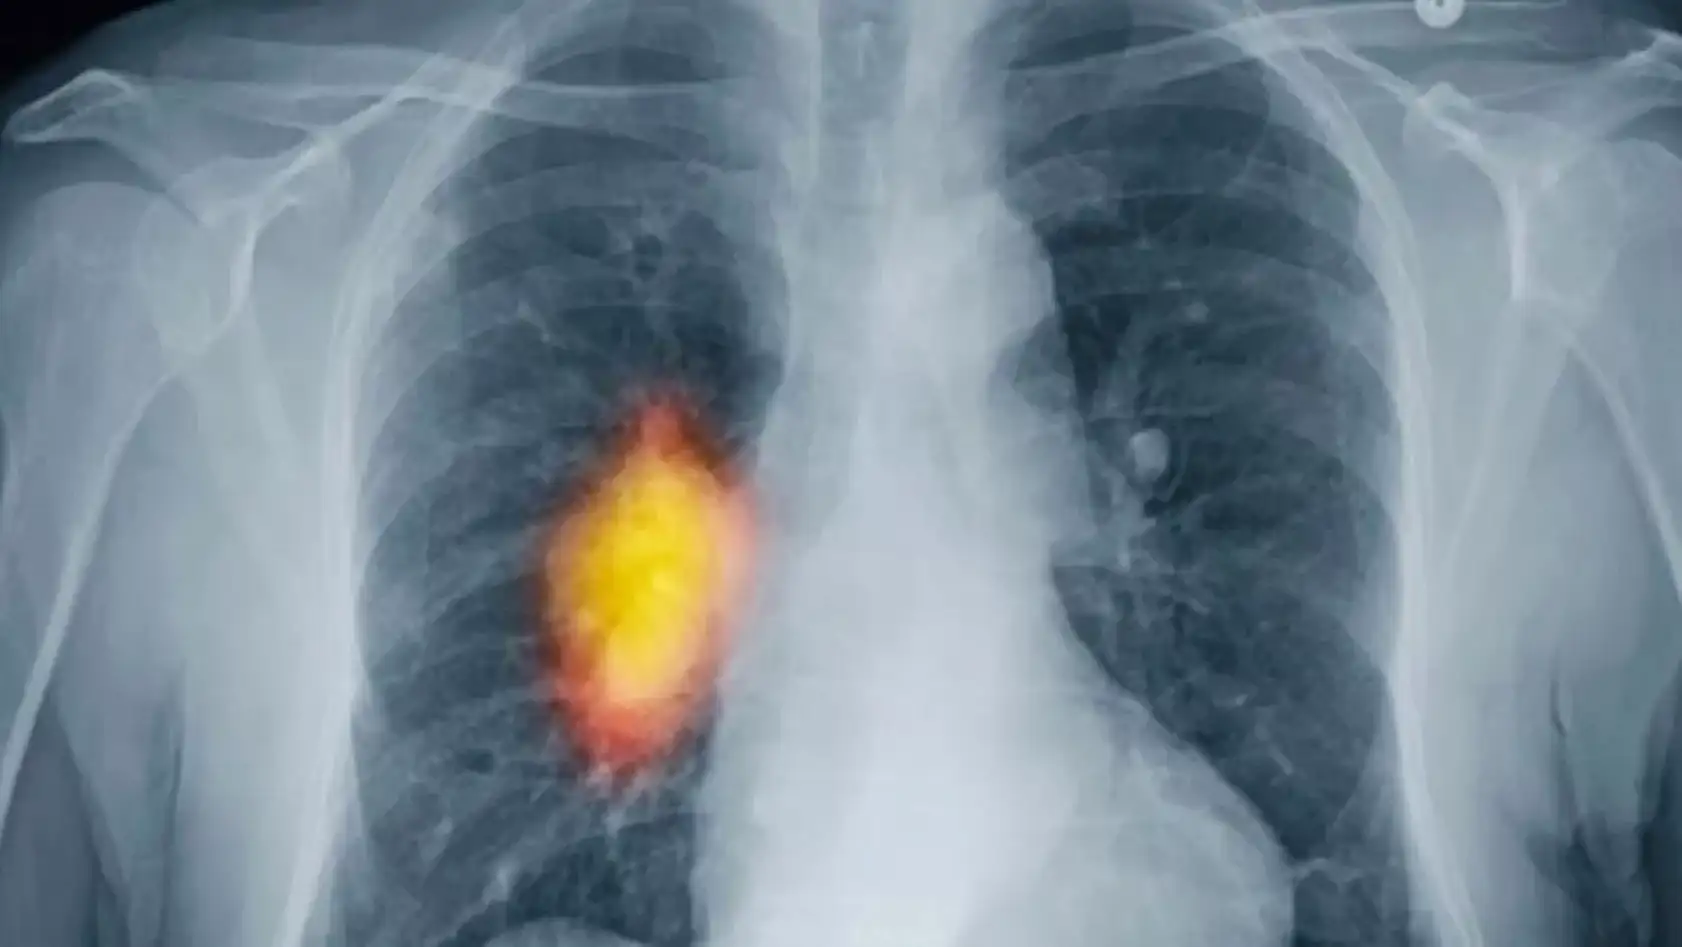

“Akciğer kanseri en çok ölüme neden olan kanser türü”

Günümüzde eskiye kıyasla daha fazla kanser görülmesi nedeniyle bunun bir halk sağlığı sorunu kabul edilerek bazı tümör türlerinde tarama programları oluşturulduğuna dikkat çeken Doç. Dr. Karakaş “Son verilere göre yılda 19.3 milyon yeni kanser vakası tespit edilmiş ve 10 milyon kişi de ne yazık ki hayatını kaybetmiştir. Hem erkek, hem de kadınlar birlikte değerlendirildiğinde akciğer kanseri en sık görülen ve en çok ölüme neden olan kanser türüdür. Erkeklerde bunu prostat ve kolorektal (bağırsak) kanserleri izler. Kadınlarda ise en sık ve ölümcül olan meme kanseridir. Kadınlarda meme kanserini, akciğer ve kolorektal (bağırsak) kanseri takip eder” dedi.